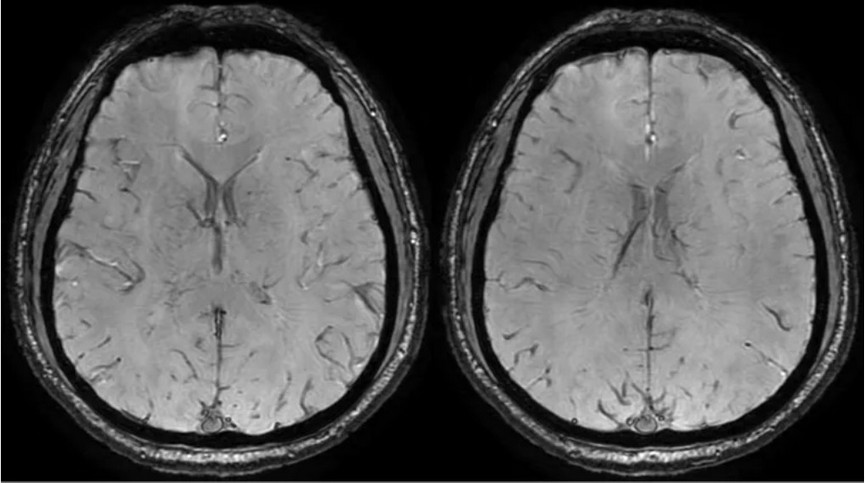

临床申请:颅脑平扫,静脉成像,磁敏感成像,颅内静脉血管黑血成像。

颅内静脉黑血成像,CUBE T1fs w/o +c,静脉窦未见异常。